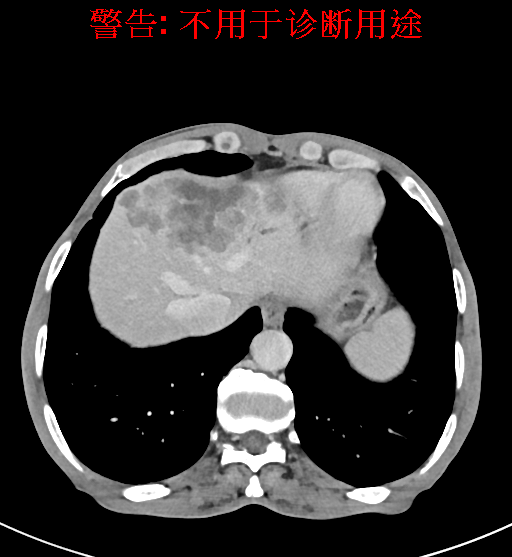

实验室检查: 血常规:WBC 4.89*109/L,RBC 3.64*1012/L, HB 119.00g/L, HCT 35.40%,PLT 123*109/L,RET% 0.48%, RET 0.017*1012/L, IRF 2.00%生化全套:ALT 56.00U/L AST 60.00U/L, LDH 312.00U/L TP 72.08g/L ALB 32.44g/L, GGT 101.00U/L,TBA 21.90umol/L,A/G 0.82,ADA 23.00U/L, PAB 94.20mg/L, CHE 5405.00U/L 肿瘤标志物:CEA 2.80ng/mL CA19-9 11.46U/ml 肝炎全套: HAV-IgM 0.21S/CO, HBcIgM 0.330S/CO, HCV-cAg 0.08S/CO, HEV-IgM 0.03S/CO, HBeAg 6.000S/CO 诊疗过程: CT结果输入海信CAS系统后行3D重建及手术规划后,于2018-5-17局麻下行“经皮肝动脉造影术+肝动脉化疗栓塞术”手术治疗 术前三维重建及手术方案设计: 将0.625mm双源薄层CT资料的静脉期和动脉期Dicom格式文件导入海信CAS系统。 通过调节窗宽窗位调整CT序号,对肿瘤,肝实质,胆囊,下腔静脉,肿瘤,肝动脉、门静脉及肝静脉等进行三维重建;系统自动计算肿瘤体积和肝脏体积。肝脏体积为1563ml,肿瘤体积为537.6ml,通过比对50-60岁正常肝脏体积为1343.28±246.69ml。 手术步骤: 常规准备后,患者仰卧于DSA手术床。常规双侧股动脉区域消毒,铺巾。2%利多卡因局部麻醉右侧股动脉区成功后,应用Seldinger技术穿刺右侧股动脉,置入5F动脉鞘。送5F 肝导管至腹腔干、肝动脉造影,肝区可见团块状及多发结节状肿瘤染色、侵犯门静脉左支。静脉推注维瑞特5mg后,透视下将微导管分别超选择至各支肿瘤供血动脉内,应用雷替曲塞4mg+奥沙利铂50mg+表柔比星20mg +LP 10ml的混合液及适量350-560um明胶海绵进行栓塞,后造影示栓塞适量,退出导管、血管鞘,局部压迫10min,加压包扎。患者术中未诉不适,术后平车安返病房。随访情况: 患者术后3月复查上腹CT示肝左叶病变活性残留,腹腔内、腹膜后多发略大淋巴结,部分较前略减小,今患者为求进一步诊治,与我院再次行“肝动脉造影+经导管肝动脉栓塞术”,术后2周无明显不适 术前CT检查:动脉期

静脉期

平衡期